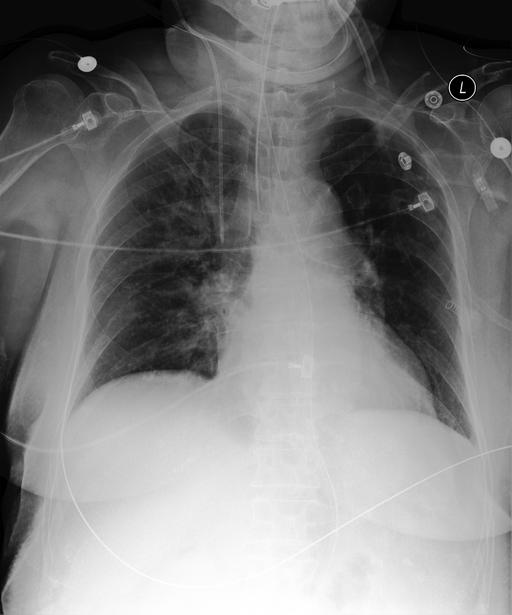

Table 6: Qualitative Examples with Concept-Specific Visual Explanations. Grad-ECLIP heat maps highlight image regions that influence the LLaVA-Med encoder’s matching between input images and SpLiCE concepts (highlighted in blue). The visualizations show which spatial features contribute to concept identification in the generated reports. Top row: Zero-Shot setting; bottom row: supervised fine-tuning setting.

Ground Truth Generated Report

Endotracheal tube terminates 2 cm above the carina. Orogastric tube terminates in the stomach. Right internal jugular catheter terminates in the mid SVC. Lungs are low in volume with stable right upper lung opacities which are better assessed on the recent chest CT but suspicious for pneumonia. There is no pneumothorax or pleural effusion. Heart is normal in size. Normal cardiomediastinal silhouette. The chest X-ray shows several findings. In the right upper zone, there is an indistinct area of opacification, which could represent a developing consolidation. Additionally, there is a right internal jugular central venous catheter with its tip at the lower superior vena cava near the cavoatrial junction. The endotracheal tube has been slightly advanced, with its tip 2.2 cm above the carina. No pneumothorax is noted, and the pulmonary vascular congestion is present. The cardiomediastinal silhouette remains unchanged.

Original Image Grad-ECLIP Activation Maps [Uncaptioned image] [Uncaptioned image] [Uncaptioned image] Endotracheal Tube Right Upper

The patient is status post median sternotomy and aortic valve replacement. Heart size is moderately enlarged but unchanged. The aorta is tortuous and calcified. There is mild interstitial pulmonary edema, relatively unchanged. At least small bilateral pleural effusions are present. Bibasilar airspace opacities may reflect compressive atelectasis. There is no pneumothorax. There is evidence of prior vertebroplasty at the thoracolumbar junction. The patient is status post median sternotomy and CABG. The heart size remains mildly enlarged. The aorta is tortuous and diffusely calcified. There is mild pulmonary edema, worse in the interval, with small bilateral pleural effusions. Bibasilar airspace opacities likely reflect atelectasis. No pneumothorax is identified. There are no acute osseous abnormalities.

Original Image Grad-ECLIP Activation Maps [Uncaptioned image] [Uncaptioned image] [Uncaptioned image] Median Sternotomy Bilateral Pleural

For each case, we select SpLiCE concepts that appear in the generated report (e.g., endotracheal tube, right upper, median sternotomy, bilateral pleural). We apply Grad-ECLIP [57] to compute the gradient of the image–text similarity score with respect to the visual features used by the LLaVA-Med vision encoder. The resulting relevance map is then upsampled and overlaid on the chest X-ray as a heat map, yielding a concept-specific visualization of which regions support that term. CEMRAG-generated reports and their corresponding concept heat maps are illustrated in Table 6 for two representative MIMIC-CXR cases, one in the Zero-shot regime and one after SFT. In each example, the left column shows the reference report, while the right column shows the CEMRAG output with the relevant concept tokens highlighted. Below these reports, we display the original image together with Grad-ECLIP maps for two selected concepts. In the Zero-shot example, concepts such as endotracheal tube and right upper are both present in the generated report and exhibit Grad-ECLIP activations that concentrate along the tracheal tube and in the right upper lung zone, respectively. In the SFT example, the concept median sternotomy yields strong activation along the midline sternal wires and retrosternal region, while bilateral pleural produces strongest activation in the lower lung zones near the right and left costophrenic angles, where pleural effusions typically accumulate. Taken together, these patterns are consistent with standard radiological practice and suggest that, when a concept appears in the report, it is usually backed by visually plausible evidence in the corresponding image regions.

These concept-specific maps serve two complementary purposes. First, they allow clinicians to verify that SpLiCE-derived concepts, when injected into the prompt, are grounded in image regions that are consistent with their radiological meaning, rather than reflecting arbitrary directions in embedding space. Second, they expose failure modes in a transparent way: if a concept is mentioned in the report but its Grad-ECLIP map does not align with plausible anatomy, this discrepancy can be inspected, questioned, and potentially used to flag low-trust outputs. At the same time, this analysis remains focused on the vision component: Grad-ECLIP explains how visual encoders support individual concepts, but does not by itself reveal how the LLM composes multiple concepts into full sentences. Extending concept-level tracing to the language component remains an important direction for future work toward fully interpretable medical VLMs.